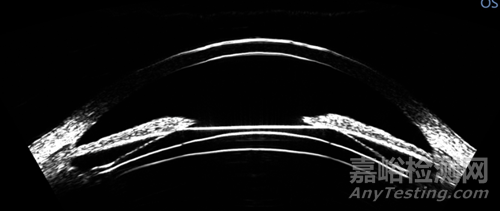

成像效果對比:

▲ArcScan Insight 100 成像結(jié)果

▲OCT成像結(jié)果

ArcScan Insight 100獨(dú)具的尺寸定型功能可輔助臨床醫(yī)生在應(yīng)用實(shí)踐中最大化降低與ICL尺寸相關(guān)的并發(fā)癥風(fēng)險(xiǎn)?;贗nsight 100針對眼內(nèi)后房的直接測量結(jié)果,為患者選取最精準(zhǔn)適宜的人工晶體。系統(tǒng)通過生成液晶級“HD”超清精顯圖像(對比其他超聲生物顯微鏡系統(tǒng)的“模擬化”成像效果),確保角膜層面的測量精度保持在1.0 µm以內(nèi),虹膜后的側(cè)向測量精度則在0.12 mm以內(nèi)。